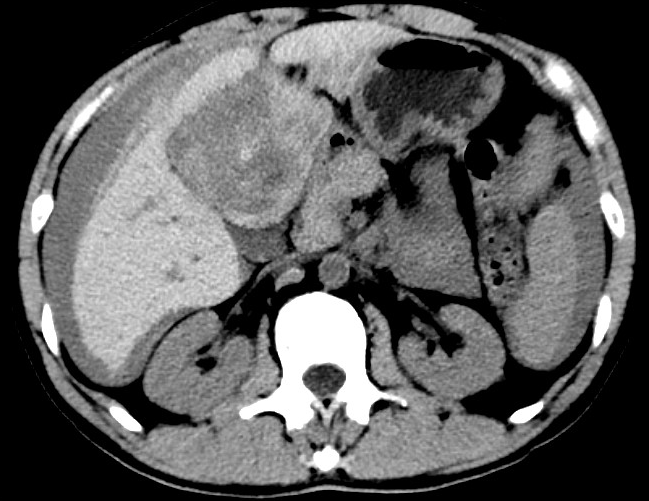

放下電話的白葦急赴消內(nèi)三搶救室會診,經(jīng)仔細查體、對患者腹部CT進行詳細閱片、綜合評估患者后,考慮患者是肝占位破裂出血?;颊卟∏槭志o急、一刻也不容耽誤,需立刻急診行肝動脈造影 栓塞術(shù)進行止血治療,在與患者家屬溝通后,立即通知消化介入室準備急診手術(shù)。

入手術(shù)室時,患者神志迷糊,口唇干燥、重度貧血貌,心電監(jiān)護提示:心率140-160次/分,血壓70/43mmHg,這是失血性休克的表現(xiàn)!白葦快速建立靜脈通道緊急給予輸血,升壓,止血等液,立即給予肝動脈造影,術(shù)中發(fā)現(xiàn)肝左葉疑似腫瘤病灶、病灶周圍血管分支有造影劑外溢,考慮血管破裂出血,迅速給予栓塞微球進行肝動脈栓塞。整個手術(shù)過程不足20分鐘,術(shù)后即刻患者心率降至100-110次/分、血壓升至90/60mmHg。

術(shù)后給予積極抗炎,止血,保肝、利尿等對癥治療,復查血常規(guī)提示活動性出血停止后,在超聲引導下行腹腔穿刺引流術(shù),術(shù)后3天共引流出血性腹水約4000ml。患者經(jīng)復查各項指標均趨于正常,復查CT提示腹腔積血已基本吸收,患者康復出院。